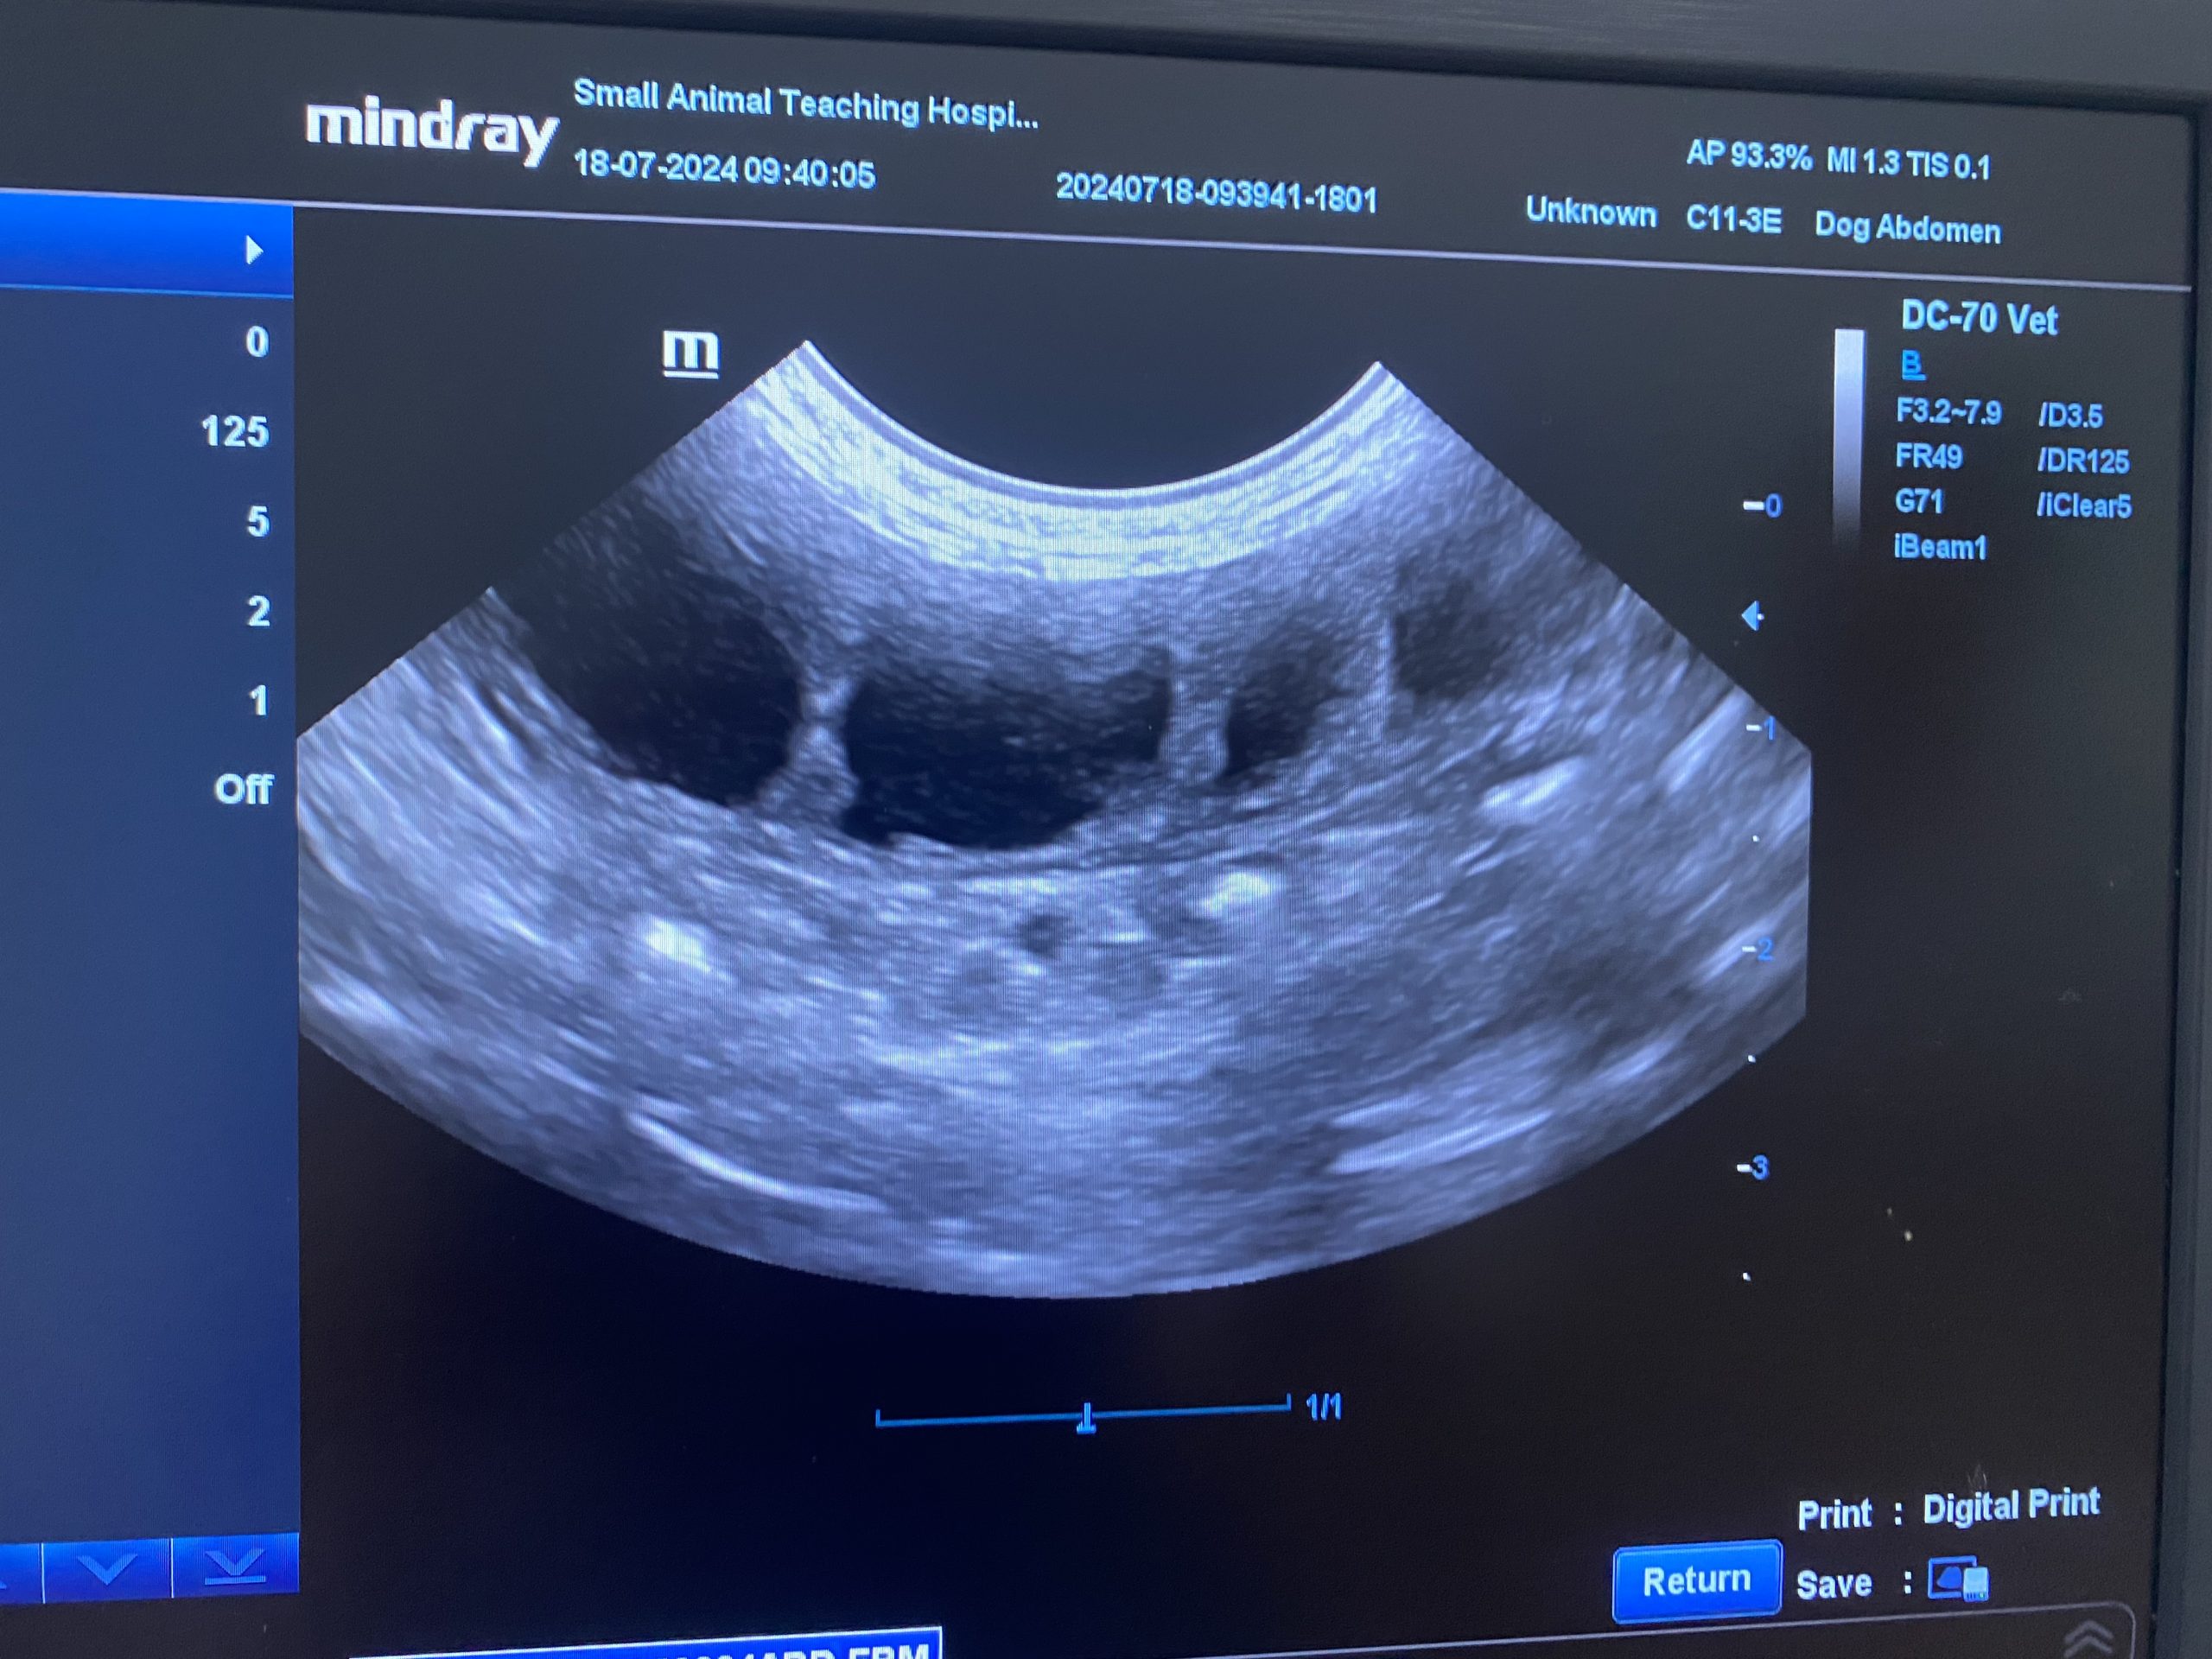

น้องสุนัขพันธุ์ชิวาว่าตัวเล็ก ถูกพาเข้ารับการรักษาที่โรงพยาบาลสัตว์ด้วยอาการ ซึม เบื่ออาหาร และมีของเหลวสีขาวขุ่นคล้ายหนองไหลออกจากอวัยวะเพศ (vaginal discharge) ทีมสัตวแพทย์ได้ทำการตรวจอัลตราซาวนด์ พบว่า มดลูกมีขนาดขยายผิดปกติจากการสะสมของของเหลว ซึ่งเป็นลักษณะของโรค มดลูกอักเสบ (Pyometra)